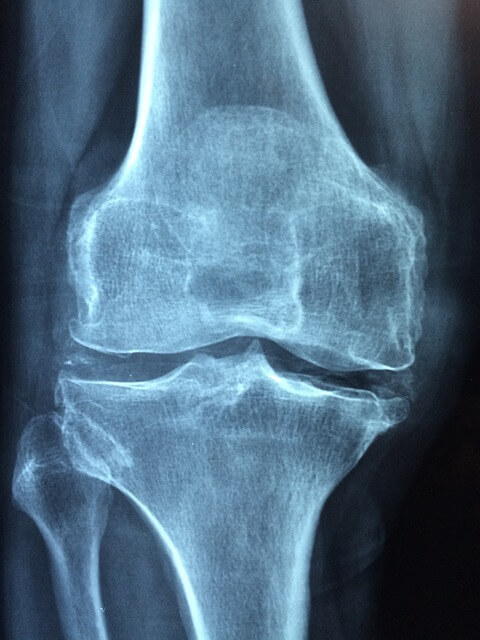

골다공증은 뼈의 양이 감소하고 얇아지며 뼈의 강도가 약해져서 골절이 일어날 가능성이 높은 상태를 말합니다. 골다공증의 정상수치와 위험요인 그리고 완치방법에 대해 자세히 살펴보겠습니다.

골다공증은 골밀도가 감소하여 부러지기 쉬운 질환입니다. 특히 중년과 노년층에서 많이 발생합니다. 골절의 경우 골다공증의 가장 흔하고 심각한 합병증입니다. 주로 척추와 고관절의 뼈가 부러집니다. 골다공증의 경우 초기에는 특별한 증상이 없어 많은 사람들이 뼈 건강이 약화되었다는 사실을 알기 어렵기 때문에 주의가 필요합니다. 특히 골다공증 위험 요인이 많은 경우 조기 예방이 필수적입니다. 골다공증을 유발할 수 있는 위험 요인으로 유전적 요인이 골다공증 발병에 중요한 영향을 미칩니다. 골다공증에 걸린 부모나 가까운 가족이 있는 경우 뼈 건강에 취약할 가능성이 높아집니다. 특히 어머니가 골다공증을 앓고 있다면 딸의 골다공증 발병 위험도 높아질 수 있습니다. 이 경우 평소보다 뼈 건강에 더 신경을 쓰고 정기적인 검사를 통해 자신의 뼈 밀도를 확인하는 것이 중요합니다. 다음으로는 생활 습관 및 영양 상태입니다. 골다공증의 주요 원인 중 하나는 잘못된 생활 습관입니다. 특히 칼슘과 비타민 D 섭취가 부족하면 뼈가 약해질 수 있으며 흡연이나 과음도 뼈 밀도를 낮추는 요인으로 작용합니다. 또한 카페인 과다 섭취는 체내 칼슘 흡수를 방해하여 뼈 건강에 부정적인 영향을 미칠 수 있습니다. 따라서 균형 잡힌 식단을 섭취하고 필요한 영양소를 충분히 섭취하는 것이 골다공증 예방에 중요합니다. 마지막으로 호르몬 변화와 연령입니다. 골다공증은 여성 호르몬인 에스트로겐의 감소와 밀접한 관련이 있습니다. 특히 여성은 폐경기를 거치면서 에스트로겐 수치가 급격히 감소하여 뼈가 약해질 가능성이 높아집니다. 남성은 나이가 들면 테스토스테론 수치가 감소하여 뼈가 약해질 수 있으므로 중년이 된 후에는 남녀 모두 주의할 필요가 있습니다. 따라서 폐경 후 여성과 노인 남성은 정기적인 검사를 통해 뼈 건강을 확인하는 것이 좋습니다. 결론적으로 골다공증은 조기 예방과 관리가 중요한 질환으로 위험 요인을 잘 파악하고 미리 대비하는 것이 중요합니다. 유전적 요인, 생활 습관, 호르몬 변화 등 위험 요인을 잘 알고 있으며, 뼈 건강을 유지하기 위해 식습관과 운동에 주의를 기울여야 합니다. 정기적인 검사를 통해 자신의 골밀도를 확인하고 전문가의 상담을 받는 것도 좋은 방법입니다.